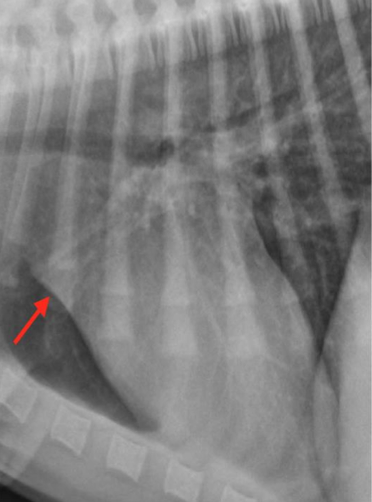

What is the arrow pointing to?

Intra-articular calcified bodies aka joint mouse